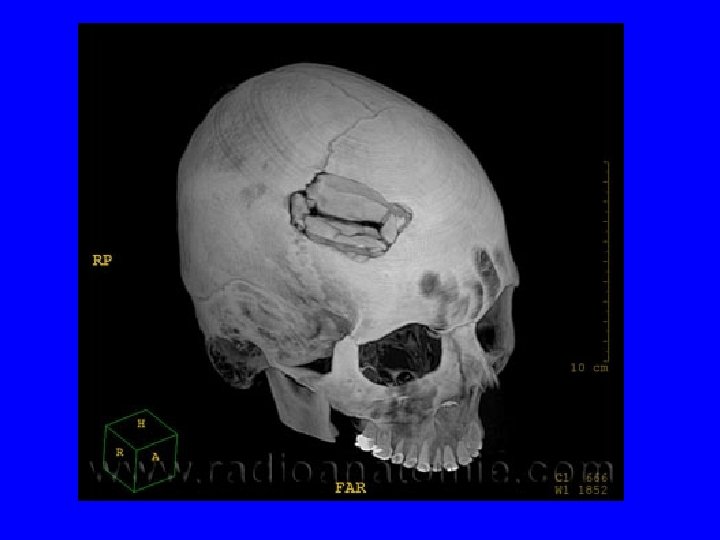

Principaux types de lésions cranio-cérébrales traumatiques • • Embarrure Plaie cranio-cérébrale Hématomes Contusion cérébrale oedémateuse et/ou hémorragique • Hémorragie méningée • F de la base du crâne avec brèche ostéoméningée

IV. Conduite thérapeutique • Indications d’intervention neurochirurgicale en urgence après un TC – HED – HSDA – Hématome intracérébral avec effet de masse – Embarrure – Plaie crânio-cérébrale